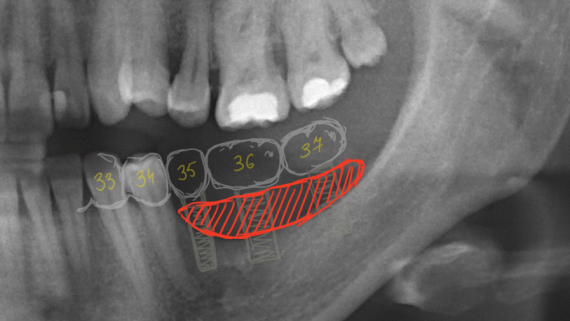

ВОКРУГ ИМПЛАНТАТОВ: нулевая утрата кости, биологическая ширина десны и всё такое…